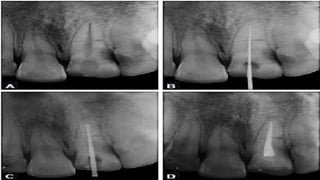

✓ Radiographic evidence:

Since root fractures are usually oblique, 3 angled

x-rays(45, 90, 110 degrees) to be taken

According to the Andreasen and Hjorting—Hansen,

root fracture can show healing in following ways:

1) Healing with calcified tissue in which fractured fragments

are in close contact

2) Healing with interproximal connective tissue in which

radiographically fragments appear separated by a radiolucent line and

the fragment edges are rounded.

1) Healing with interproximal bone and connective

tissues.

Here fractured fragments are seen separated by a distinct bony

bridge radiographically.

All the 3 types considered success

✓ Interproximal inflammatory tissue without healing,

radiographically it shows widening of fracture line

• Healing pattern of Root Fracture